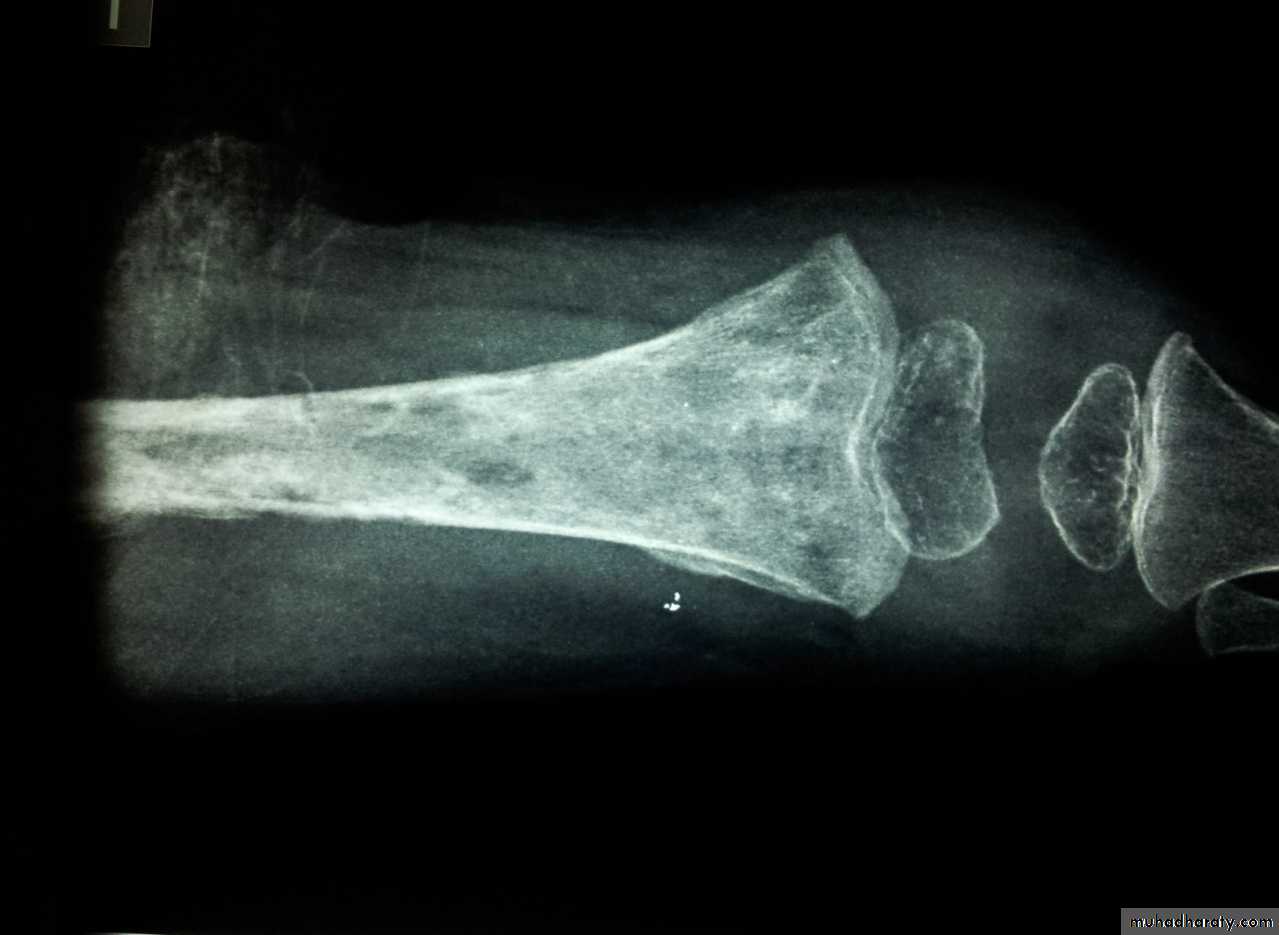

Sub-acute heamatogenous osteomyelitis [Brodies abscess]

Sometimes because of the low virulence of the microorganism and good resistance of the host; a mild form of osteomyelitis is found.Incidence:

Patient is usually child or adolescent.

X-Ray

Typically shows small oval radiolucent area surrounding by sclerotic bone (the classical brodies abscess).

Differential diagnosis:

It is early mistaken far osteoma (a benign bone tumour) diagnosis is made after exploration.Treatment:

The abscess is surgically opened under antibiotic cover.